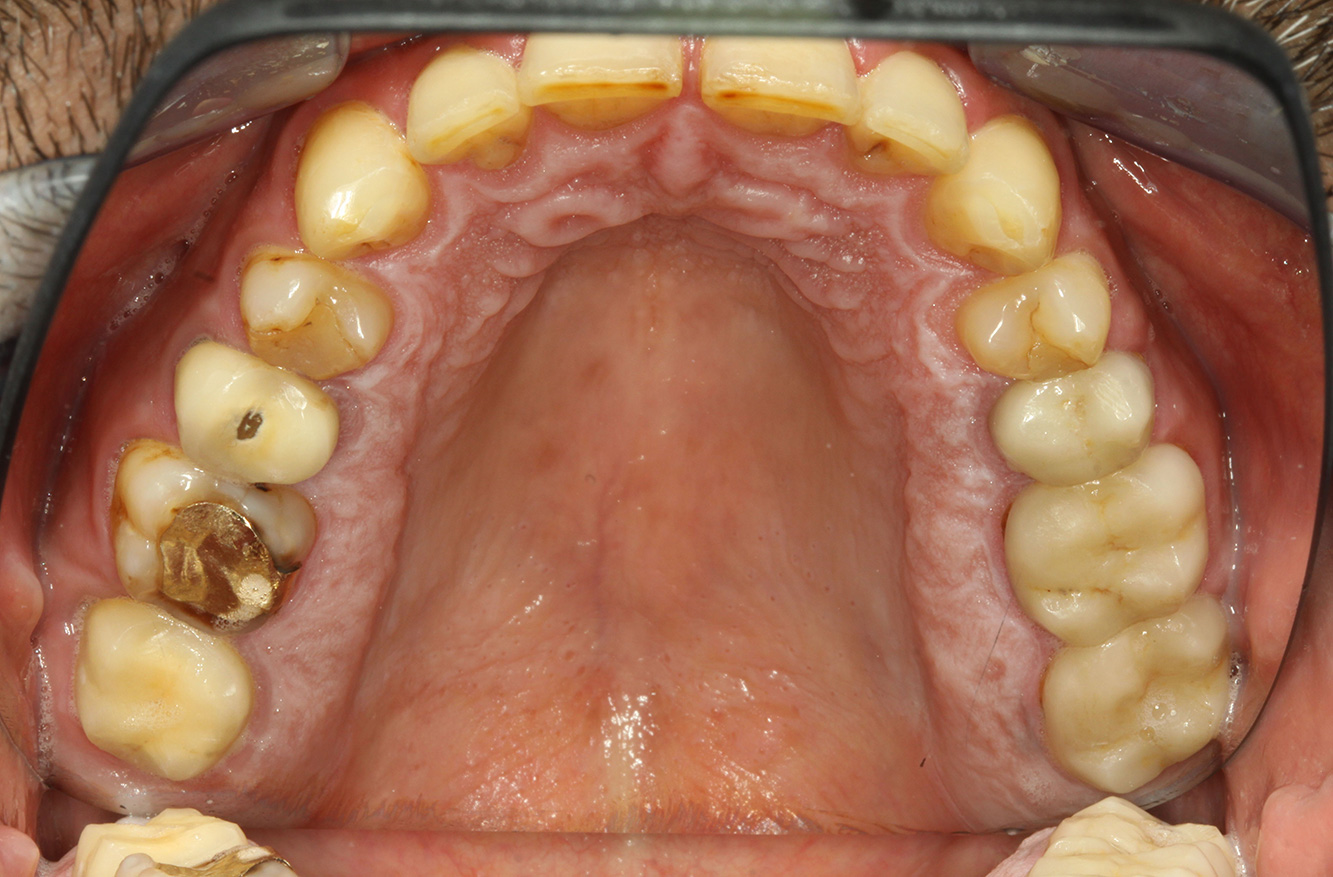

Il paziente ha 39 anni e in passato è stato sottoposto ad un intervento per la sostituzione della valvola aortica dovuta a insufficienza valvolare ed endocardite. Assume regolarmente l'ASS 100 come anticoagulante. Per quel che riguarda lo stile di vita, il regime alimentare seguito dal paziente è classificato come “dieta che favorisce la formazione della carie”, per via del consumo regolare di cibi ad alto contenuto di zuccheri e dei sei-sette pasti consumati al giorno. La salute orale del paziente indica un rischio moderato di carie, con lesioni attive. Il rischio di parodontite è basso, tuttavia il paziente è affetto da gengivite. Si formulano quindi i seguenti consigli per il trattamento di profilassi.

Per la seduta di profilassi non si possono formulare consigli per strumenti specifici. Si può ricorrere a un'applicazione mirata di air-polishing e lucidatura con testina rotante per rimuovere delicatamente placca e discromie lungo i margini del restauro e per ridurre le nicchie dove i batteri cariogeni possono formare nuove colonie (19).

Si consiglia una fluorizzazione per stimolare ulteriormente la prevenzione della carie, prevenire in particolar modo nuove formazioni intorno ai margini del restauro e per sigillare le superfici radicolari. Entrambi i provvedimenti possono ridurre la sensibilità dei denti alla temperatura.

A causa delle lesioni cariose attive e del rischio ad esse associato di progressione, si consiglia un intervallo di richiamo ravvicinato di tre-quattro mesi.